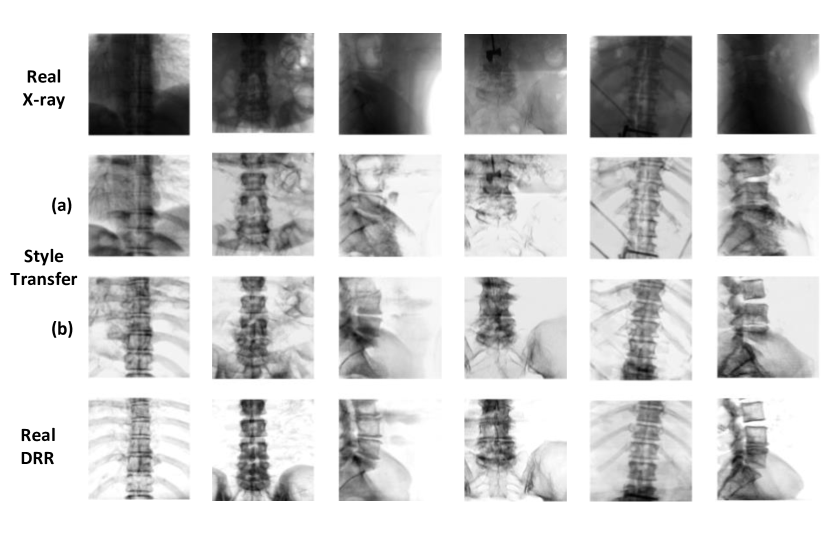

We compare our pixel space adaptation using CUT network [36] with supervised pix2pix network [18] for registration performance (Table 1) and X-ray to DRR style transfer (Figure 6). Our proposed unsupervised pixel space domain adaptation matches closely to the supervised style transfer network both in registration performance (Table 1) and the image appearance (Figure 6) indicating we are close to the maximum performance achievable for domain adaptation using style transfer.

Refer to caption

Figure 6: X-ray to DRR style transfer using (a) unsupervised CUT network (b) supervised pix2pix network along with real DRR. Each column indicates a test data sample.